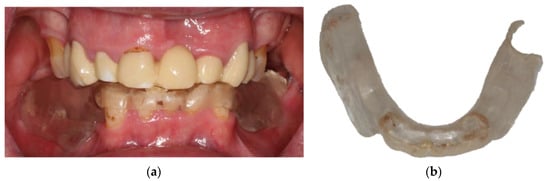

3. Case Report

- Locator abutments on both implants, single-crown FDPs on the remaining lower molar teeth, insertion of a tooth-colored and tooth-shaped monolithic RDP fabricated from POM with minimally invasive preparation of the lower anterior teeth (experimental character in long-term endurance).